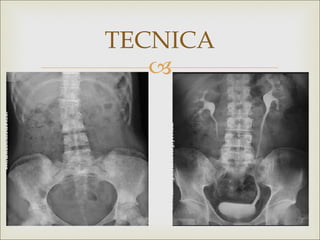

TECNICA

RX SIMPLE DE ABDOMEN   Placa RUV  Permite obtener una visión convencional de las estructuras esqueléticas, intraabdominales y de las vías urinarias  Estudios sin medio de contraste y no invasivo  sencillo

INDICACIONES   Detección de urolitiasis  Evaluar cuerpos extraños en al aparato urinario  Examinar posición o colocación de catéteres  Para diagnosticar íleos paralíticos u obstrucciones intestinales.